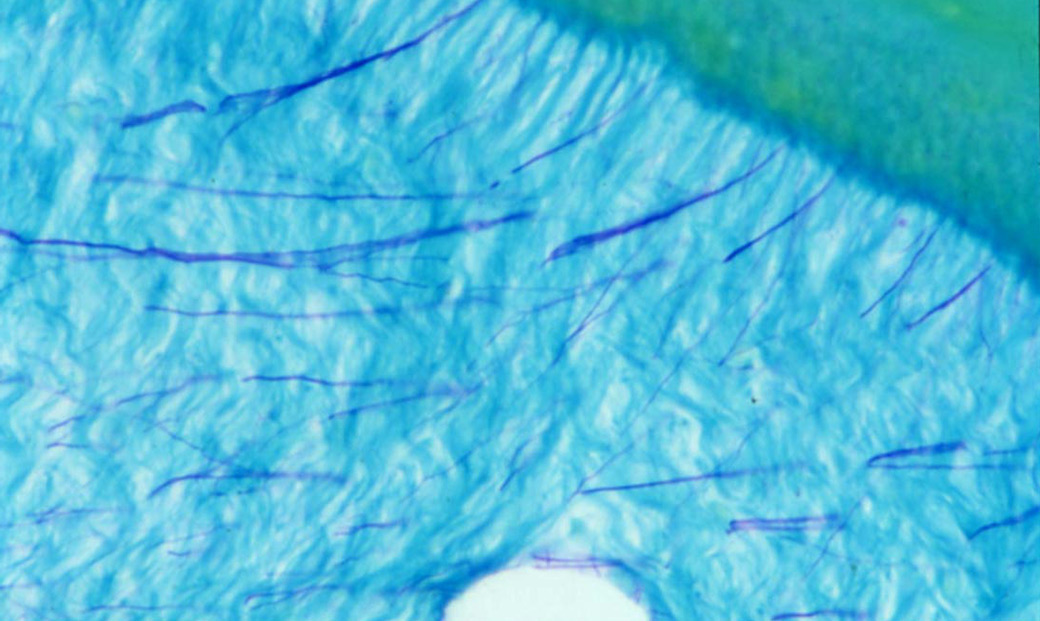

Desmodontale Oxytalanfasern im Parodont von Affen (Oxone-Aldehyd-Fuchsin-Halmi-Technik).

Mit freundlicher Genehmigung von Prof. Dr. med. dent. Dr. h. c. mult. Anton Sculean, M.S., Universität Bern, Schweiz. Aktuelle Kurse unter Leitung von Professor Sculean finden Sie hier.